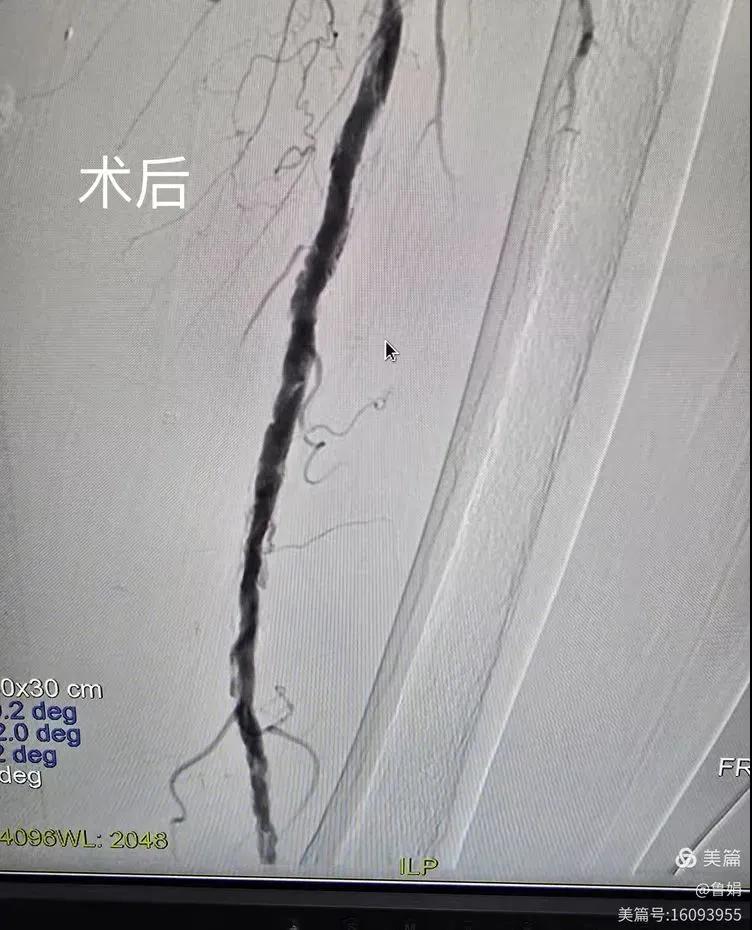

據(jù)悉,該患者,女,73歲,下肢動(dòng)脈硬化閉塞癥,“以靜息痛,間歇性跛行”入院,CTA評(píng)估:股淺動(dòng)脈,腘動(dòng)脈間斷性多段重度狹窄,外二科血管外科團(tuán)隊(duì)根據(jù)患者病情,結(jié)合檢查結(jié)果,經(jīng)過(guò)科室會(huì)診后,決定對(duì)該病人行介入治療。手術(shù)由周創(chuàng)業(yè)副主任與北大一院血管外科專家郭宏杰教授聯(lián)合開(kāi)展,對(duì)股淺動(dòng)脈,腘動(dòng)脈重度閉塞段行血管開(kāi)通+藥涂球囊擴(kuò)張成形,術(shù)后狹窄明顯緩解,血流恢復(fù)!